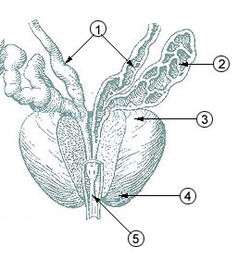

Prostate with seminal vesicles and seminal ducts, viewed from in front and above. | |

Structure of the penis Lobes of prostate

Fundus of the bladder with the vesiculæ seminales. Vesiculae seminales and ampullae of ductus deferentes, front view.

Vesiculae seminales and ampullae of ductus deferentes, front view. Vertical section of bladder, penis, and urethra.